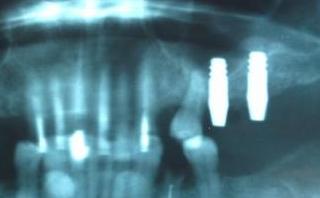

限界に近い ソケットリフト症例 (2)

左上奥歯が痛くて噛めないということで 抜歯をしてインプラント3本を入れることにしました

殆どシュナイダー膜剥き出しのケースでしたが、ソケットリフトで対応できました